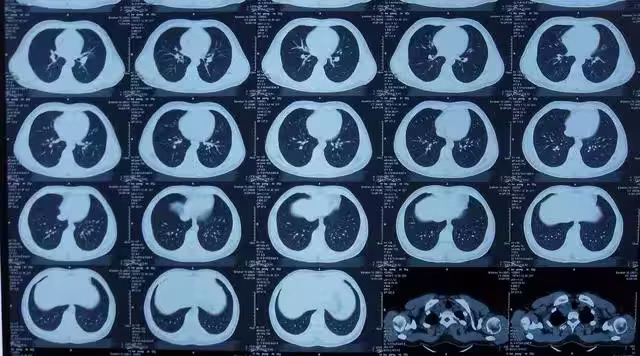

事實上,CT檢查仍然存在患癌症的風險,根據相關研究,一次效劑量為10mSv的成人腹部CT檢查將使癌症風險增加1/2000。

此外,國際輻射防護委員會(I-CRP)的研究數據表明,CT全身掃描體檢將使受檢者的輻射致癌風險增加約8%。

這意味著,如果一個人經常接受CT檢查,他們患癌症和遺傳病的風險會隨著接觸次數的增加而增大。